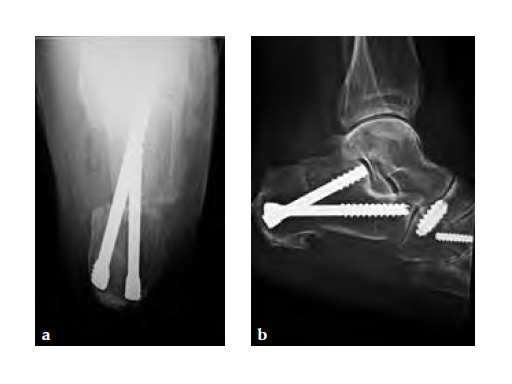

A medializing calcaneal osteotomy was performed and fixed with two 6.5 mm HCS, a flexor hallucis longus transfer to her navicular is secured with an interference 7 mm screw and a lapidus procedure fixed with two crossing 4.5 HCS (see Fig 2a-b).

Progressive weight bearing was permitted at 8 weeks and UCBL was advised until the fourth postoperative month (see Fig 3a-b).